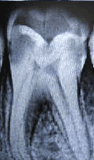

Decayed Molar |